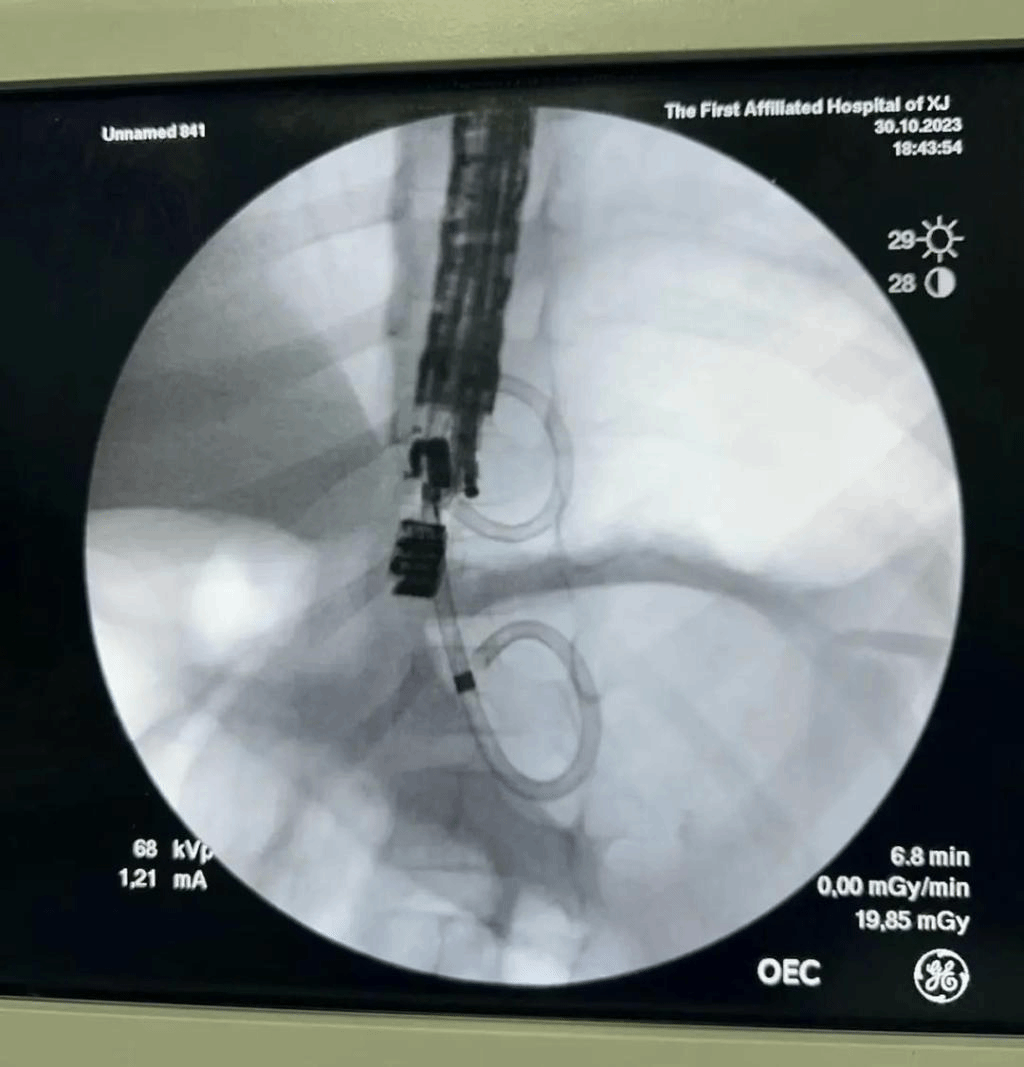

5岁的孩子不慎摔伤导致上腹部腹痛,并伴有呕吐和发热症状,经检查医生判断其为胰腺假性囊肿(截面大小约7.0cm*6.3cm)、胰管断裂可能。考虑到患儿年龄小,且囊肿已经形成完整囊壁包膜,经新医大一附院消化病中心内镜团队充分评估后,决定采取超声内镜进行探查,通过胃体部位超声检查准确定位胰腺囊肿穿刺部位,经胃壁穿刺成功后,再在X线下置入导丝,切开刀扩大穿刺口,成功置入双猪尾引流支架,见清亮囊液流出,仅30分钟便顺利完成手术。术后复查胰腺囊肿较前明显缩小,患儿无任何不适,很快康复出院。